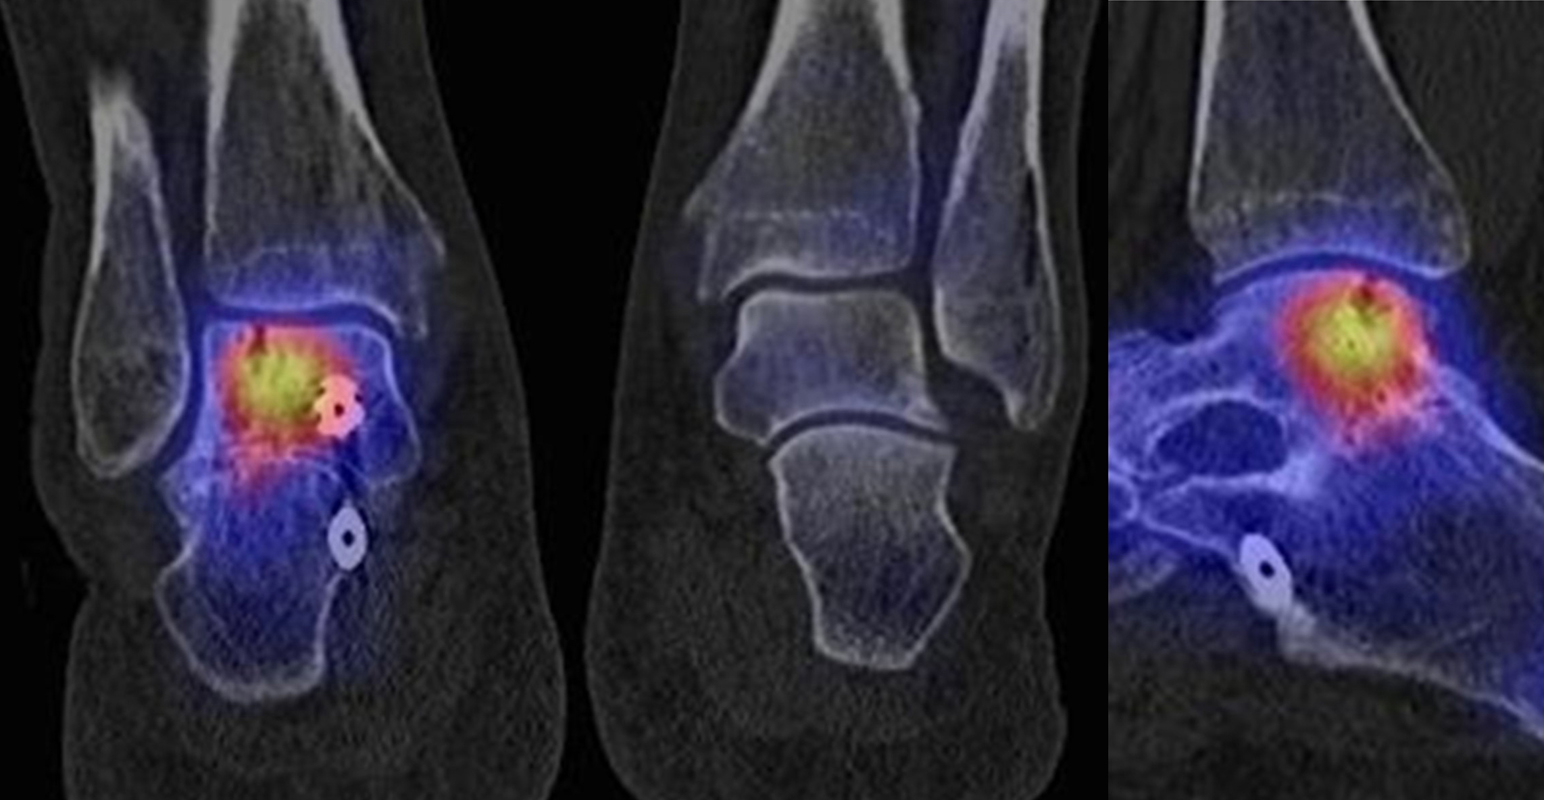

SPECT/CT zur Beurteilung von Endoprothesen

Weltweit nimmt die Prävalenz von Sprunggelenk-Prothesen durch Verbesserungen der Implantate und chirurgischen Techniken zu. Trotzdem berichtet ein signifikanter Anteil von Patienten über persistierende Beschwerden nach Prothesen-Implantation, sodass in der Literatur über Revisionsraten in bis zu 39 % der Fälle berichtet wird 5051. Die Ermittlung der Schmerzquelle mit den konventionellen bildgebenden Verfahren (Röntgen, CT, MRT (auch mit Metall-Artefakt-Reduktion)) ist begrenzt, so dass hier die SPECT/CT die Aussagekraft ähnlich wie bei der Beurteilung anderer Prothesen (z. B. Knie und Hüfte) signifikant erhöht. Verschiedenste Fragestellungen müssen bei der Evaluation einer schmerzhaften Sprunggelenk-Prothese beantwortet werden: Achsenstellung, Prothesenlage, Impingement, Lockerung, Senkung von Prothesenkomponenten, Frakturen, Zysten, Osteolysen, Anschlussarthrosen, Infektionen, Nervenschäden, CRPS, Materialunverträglichkeiten.

Zur Zuordnung von Mehrspeicherungen und morphologischen Veränderungen im Bereich von Prothesen eignen sich folgende Kriterien 51:

• Flächiger starker Fokus am Prothesen-Knochen-Interface → V. a. Lockerung

• Fokus medial oder lateral am Prothesen-Knochen-Interface → V. a. fokaler biomechanischer Stress aufgrund von Fehlstellung der Prothese oder des Rückfußes

• Fokus medial oder lateral im Gelenkabschnitt / Zone zwischen Talus und den Malleolen → Ausdruck eines Impingement

• Im CT zart randsklerosierte rundliche Osteolyse(n) am Prothesen-Knochen-Interface mit metabolischem Fokus → V. a. symptomatische Zyste

• Fokale oder flächige Mehranreicherungen in angrenzenden Gelenken in Verbindung mit arthrotischen Veränderungen im CT → V. a. symptomatische Arthrose

Beispiele für SPECT/CT-Untersuchungen nach OSG-TEP sind in den Abbildungen 6.1. bis 6.3. abgebildet.

Gurbani et al. evaluierten 37 Patienten mit schmerzhaften Sprunggelenkprothesen mit SPECT/CT und korrelierten die Ergebnisse mit klinischen und intraoperativen Befunden. Die SPECT/CT-Ergebnisse korrelierten zu 89,2 % (33/37 Pat.) mit der definitiven Diagnose. 28 Patienten wurden operativ revidiert und der Vergleich der SPECT/CT-Befunde mit den intraoperativen ergab eine Übereinstimmung von 92,9 % (26/28 Pat.). Die SPECT/CT identifizierte in den meisten Fällen aseptische Lockerungen (12/33 Pat.) und Impingement (11/33 Pat.). Seltenere Diagnosen waren Fehlstellungen (4/33 Pat.), Zystenbildungen (2/33 Pat.), subtalare Arthrosen (2/33 Pat.) und Infektionen (2/33 Pat.) 51.

Die Autoren beschreiben einen Fall, der neben einem Fokus am lateralen Malleolus auch eine starke flächige Anreicherung am talaren Prothesen-Knochen-Interface 17 Monate nach TEP-Implantation aufwies, so dass neben dem Verdacht auf ein laterales Impingement auch der Verdacht auf eine Lockerung der talaren Prothesenkomponente geäußert wurde. Intraoperativ bestätigte sich die Lockerung der talaren Prothesenkomponente nicht, sondern nur das laterale Impingement, welches mittels Debridement erfolgreich therapiert wurde 51. Da der Pat. bereits vor der TEP-Implantation eine Triple-Arthrodese erhalten hatte (welche im SPECT/CT unauffällig war), kann eine solche flächige Mehrspeicherung auch als weitgehend asymptomatische Stressreaktion gewertet werden.

Mertens et al. 52 berichten unter Anwendung eines standardisierten Auswerte-Schemas über eine Treffsicherheit von 96 % (Sensitivität 100 %, Spezifität 80 %) des SPECT/CT zur Diagnose der Ursachen für eine schmerzhafte Sprunggelenkprothese (n=24). Der SPECT/CT-Befund führte in 86 % zu einer spezifischen Therapie, welche in 83 % der Fälle zum Therapieerfolg führte.

Eine Analyse von Mason et al. 53 von 14 Patienten mit schmerzhaften Sprunggelenksprothesen, welche mittels SPECT/CT untersucht wurden, fanden in 13/14 Patienten ein SPECT/CT-Korrelat für die Beschwerden, wobei bei 12 Patienten der Fokus talar medial lokalisiert war. 8 Patienten wurden operativ revidiert und der Fokus entsprach einer verminderten bzw. fehlenden ossären Integration der talaren Prothesen-Komponente.